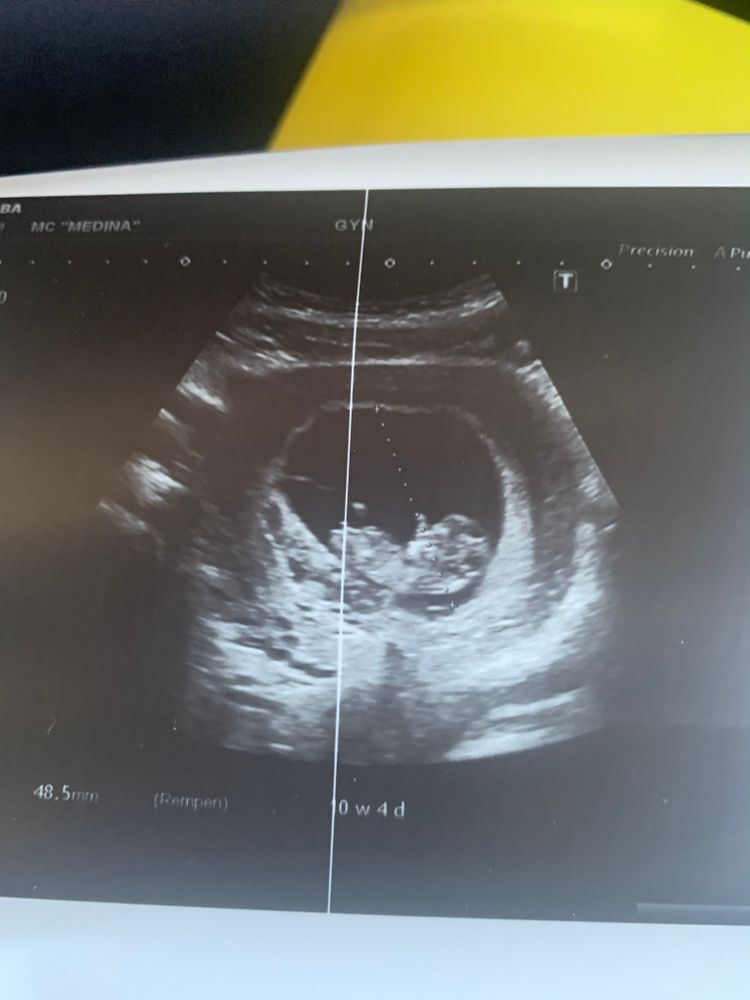

Я думаю рано для определения ,но вроде бы торчком как у мальчика

Вроде похоже на мальчика, но 10 недель прям экстремально для ввявления🙈

Daria, я знаю что очень рано, но вроде как по половому бугорку можно предположить )